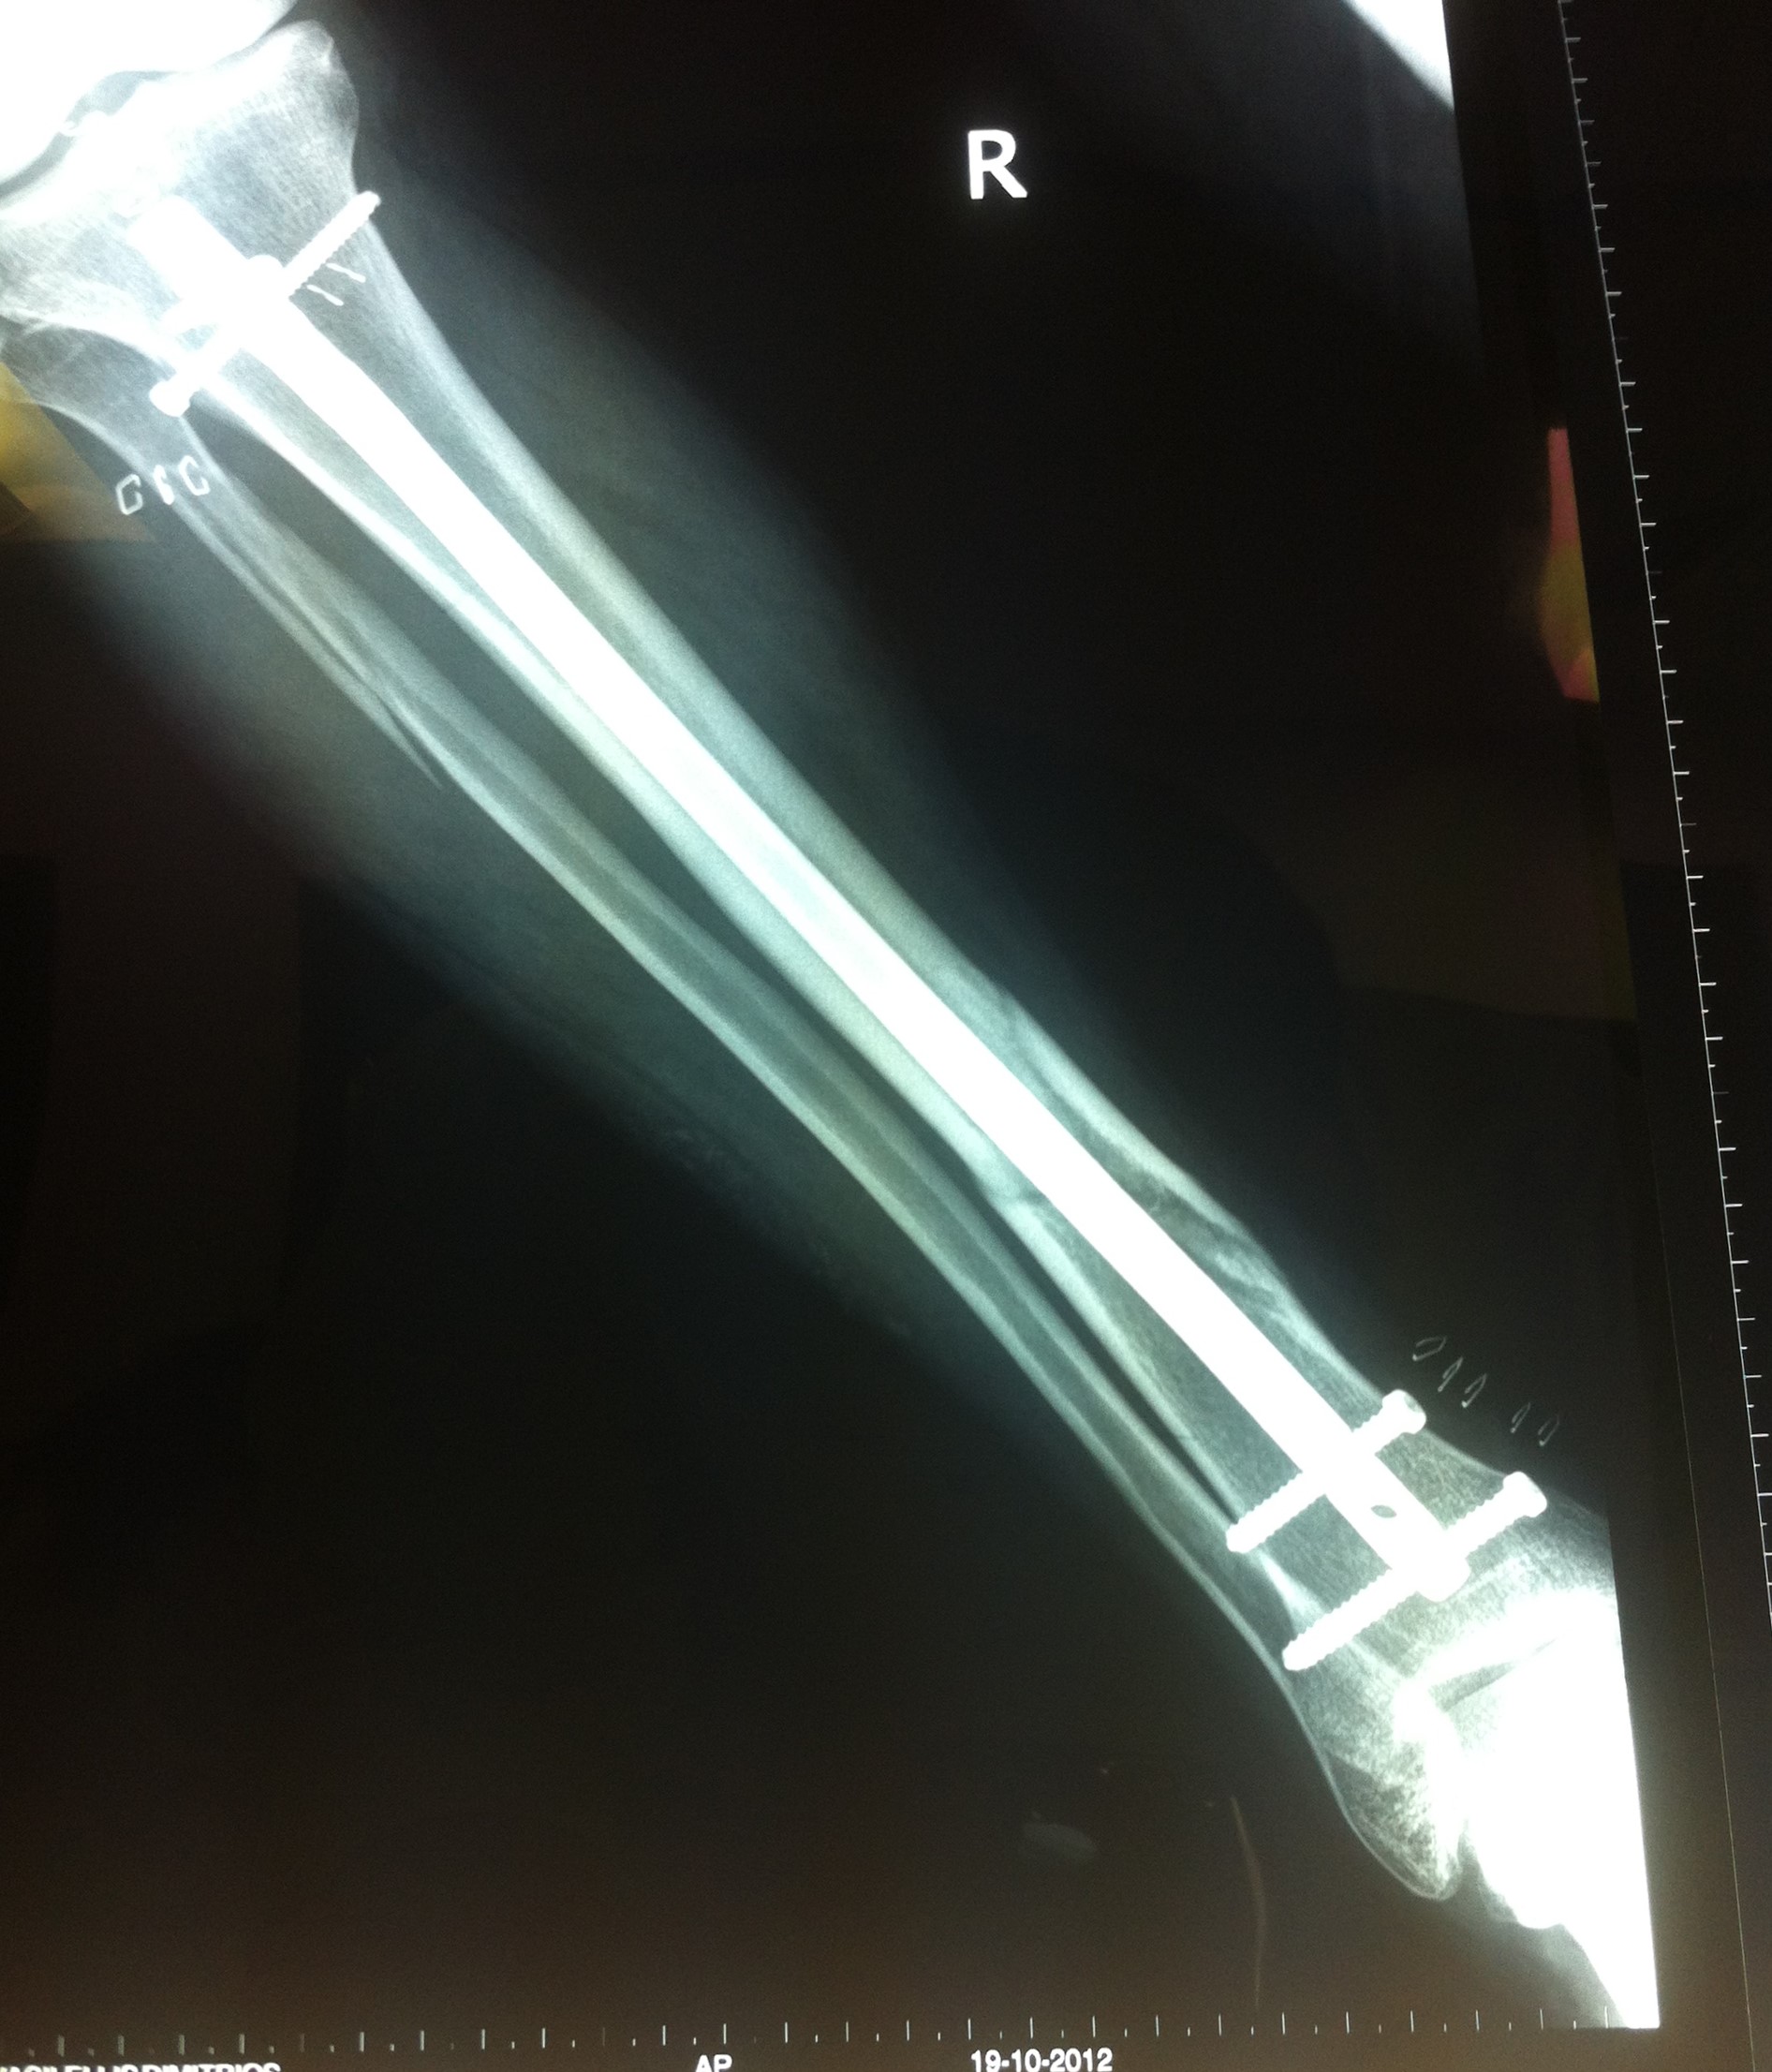

Από την άλλη, η χειρουργική μέθοδος που θα επιλεχθεί εξαρτάται από τον τύπο του κατάγματος, τις λοιπές συνοδές κακώσεις και την εμπειρία του χειρουργού. Ένα κάταγμα κνήμης μπορεί να αποκατασταθεί με τοποθέτηση ενδομυελικού ήλου, με ανοικτή ανάταξη και εσωτερική οστεοσύνθεση με πλάκες και βίδες ή με εξωτερική οστεοσύνθεση.